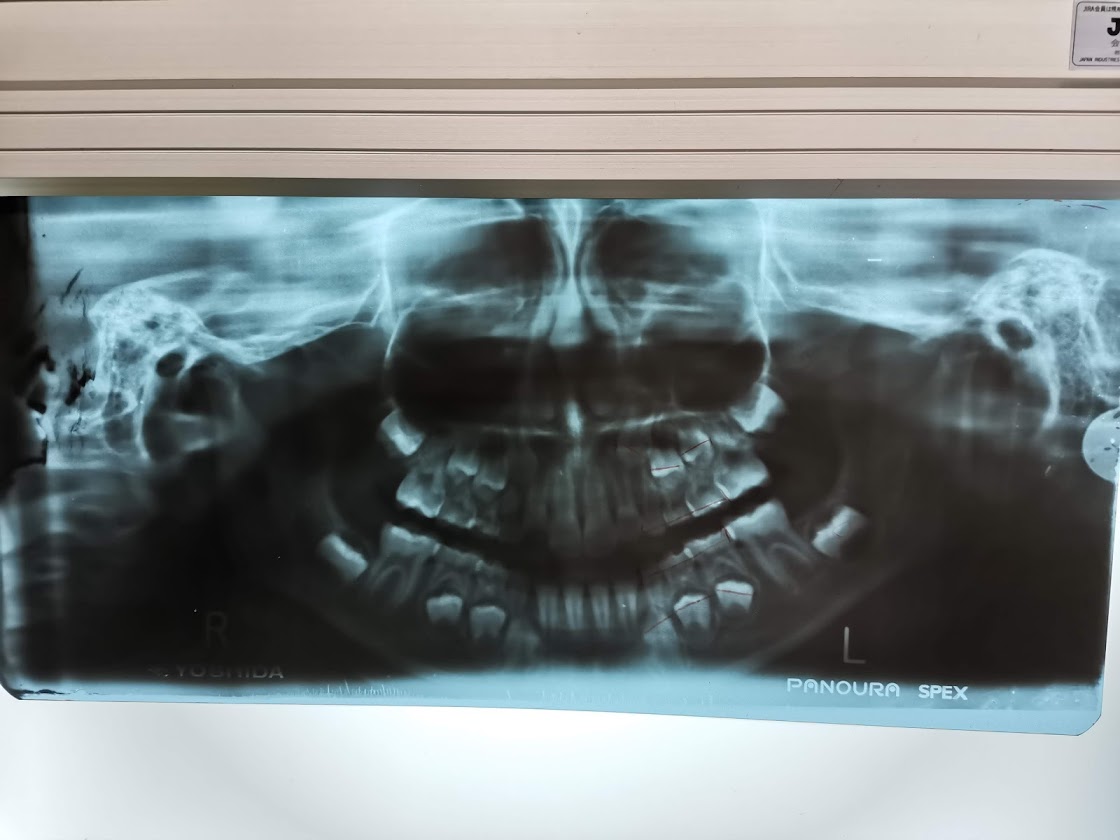

この回は一通り検査ということでしたので、1時間くらいかけてレントゲンをあれこれ撮ったり、歯形を作ったり。